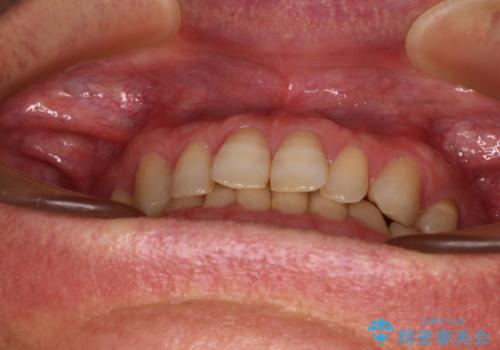

- 前歯のデコボコと隙間の空いた歯列を気にして来院された患者様です。

下顎前歯が隠れるほどのディープバイトにより、強い咬合力と突き上げで上顎歯列に隙間が空いている状態でした。

手前に傾斜している奥歯をワイヤー装置で立ち上がらせ、咬み合わせの高さを挙上することで突き上げを解消し、空隙歯列を改善していくこととしました。